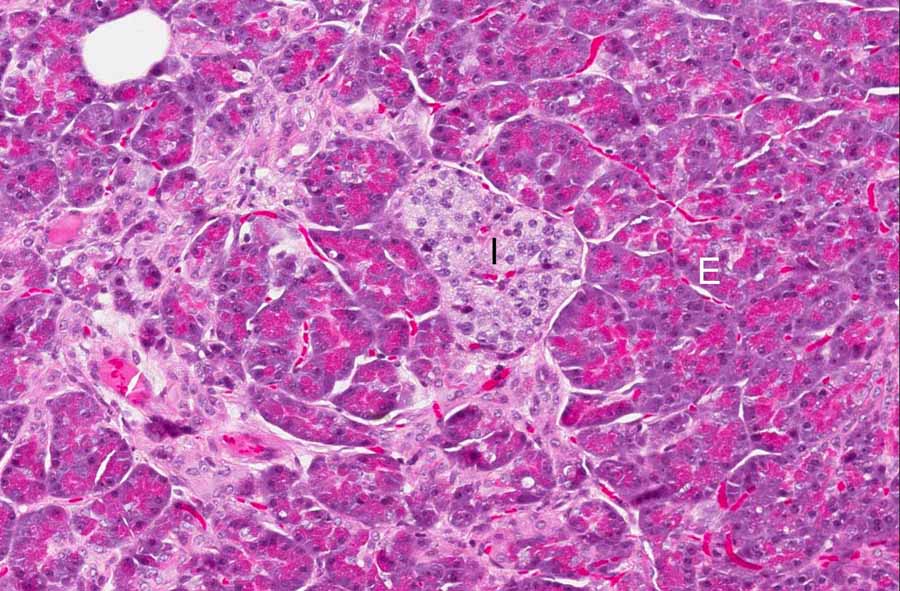

Area 4: This image is taken at the residual normal pancreatic parenchyma at the rim of the tumor. Note exocrine component (E) and the islets of Langerhans (I).

Hematoxylin & eosin

• Residual pancreatic tissue with islets and exocrine glands can be recognized at the rim of the tumor (Area 4).